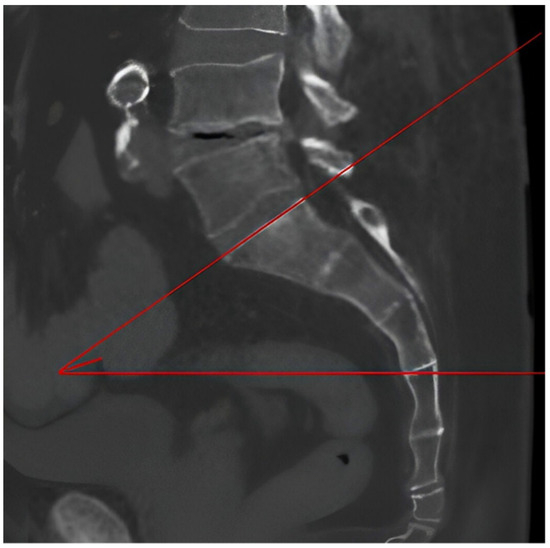

2.2. Measurements

| Sacral Slope | 41.62° ± 7.70° (40.27°–42.97°) | 40.35° ± 6.20° (39.14°–41.56°) | 0.915 |

| Pelvic Tilt | 9.80° ± 4.68° (8.90°–10.70°) | 9.91° ± 5.45° (8.84°–10.98°) | 0.917 |

| Pelvic Incidence | 50.57° ± 10.24° (48.77°–52.37°) | 50.11° ± 9.80° (48.19°–52.03°) | 0.728 |